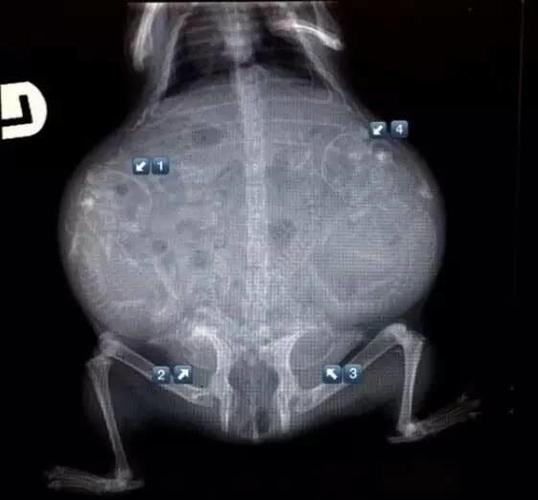

17种怀孕动物x光照片,大开眼界